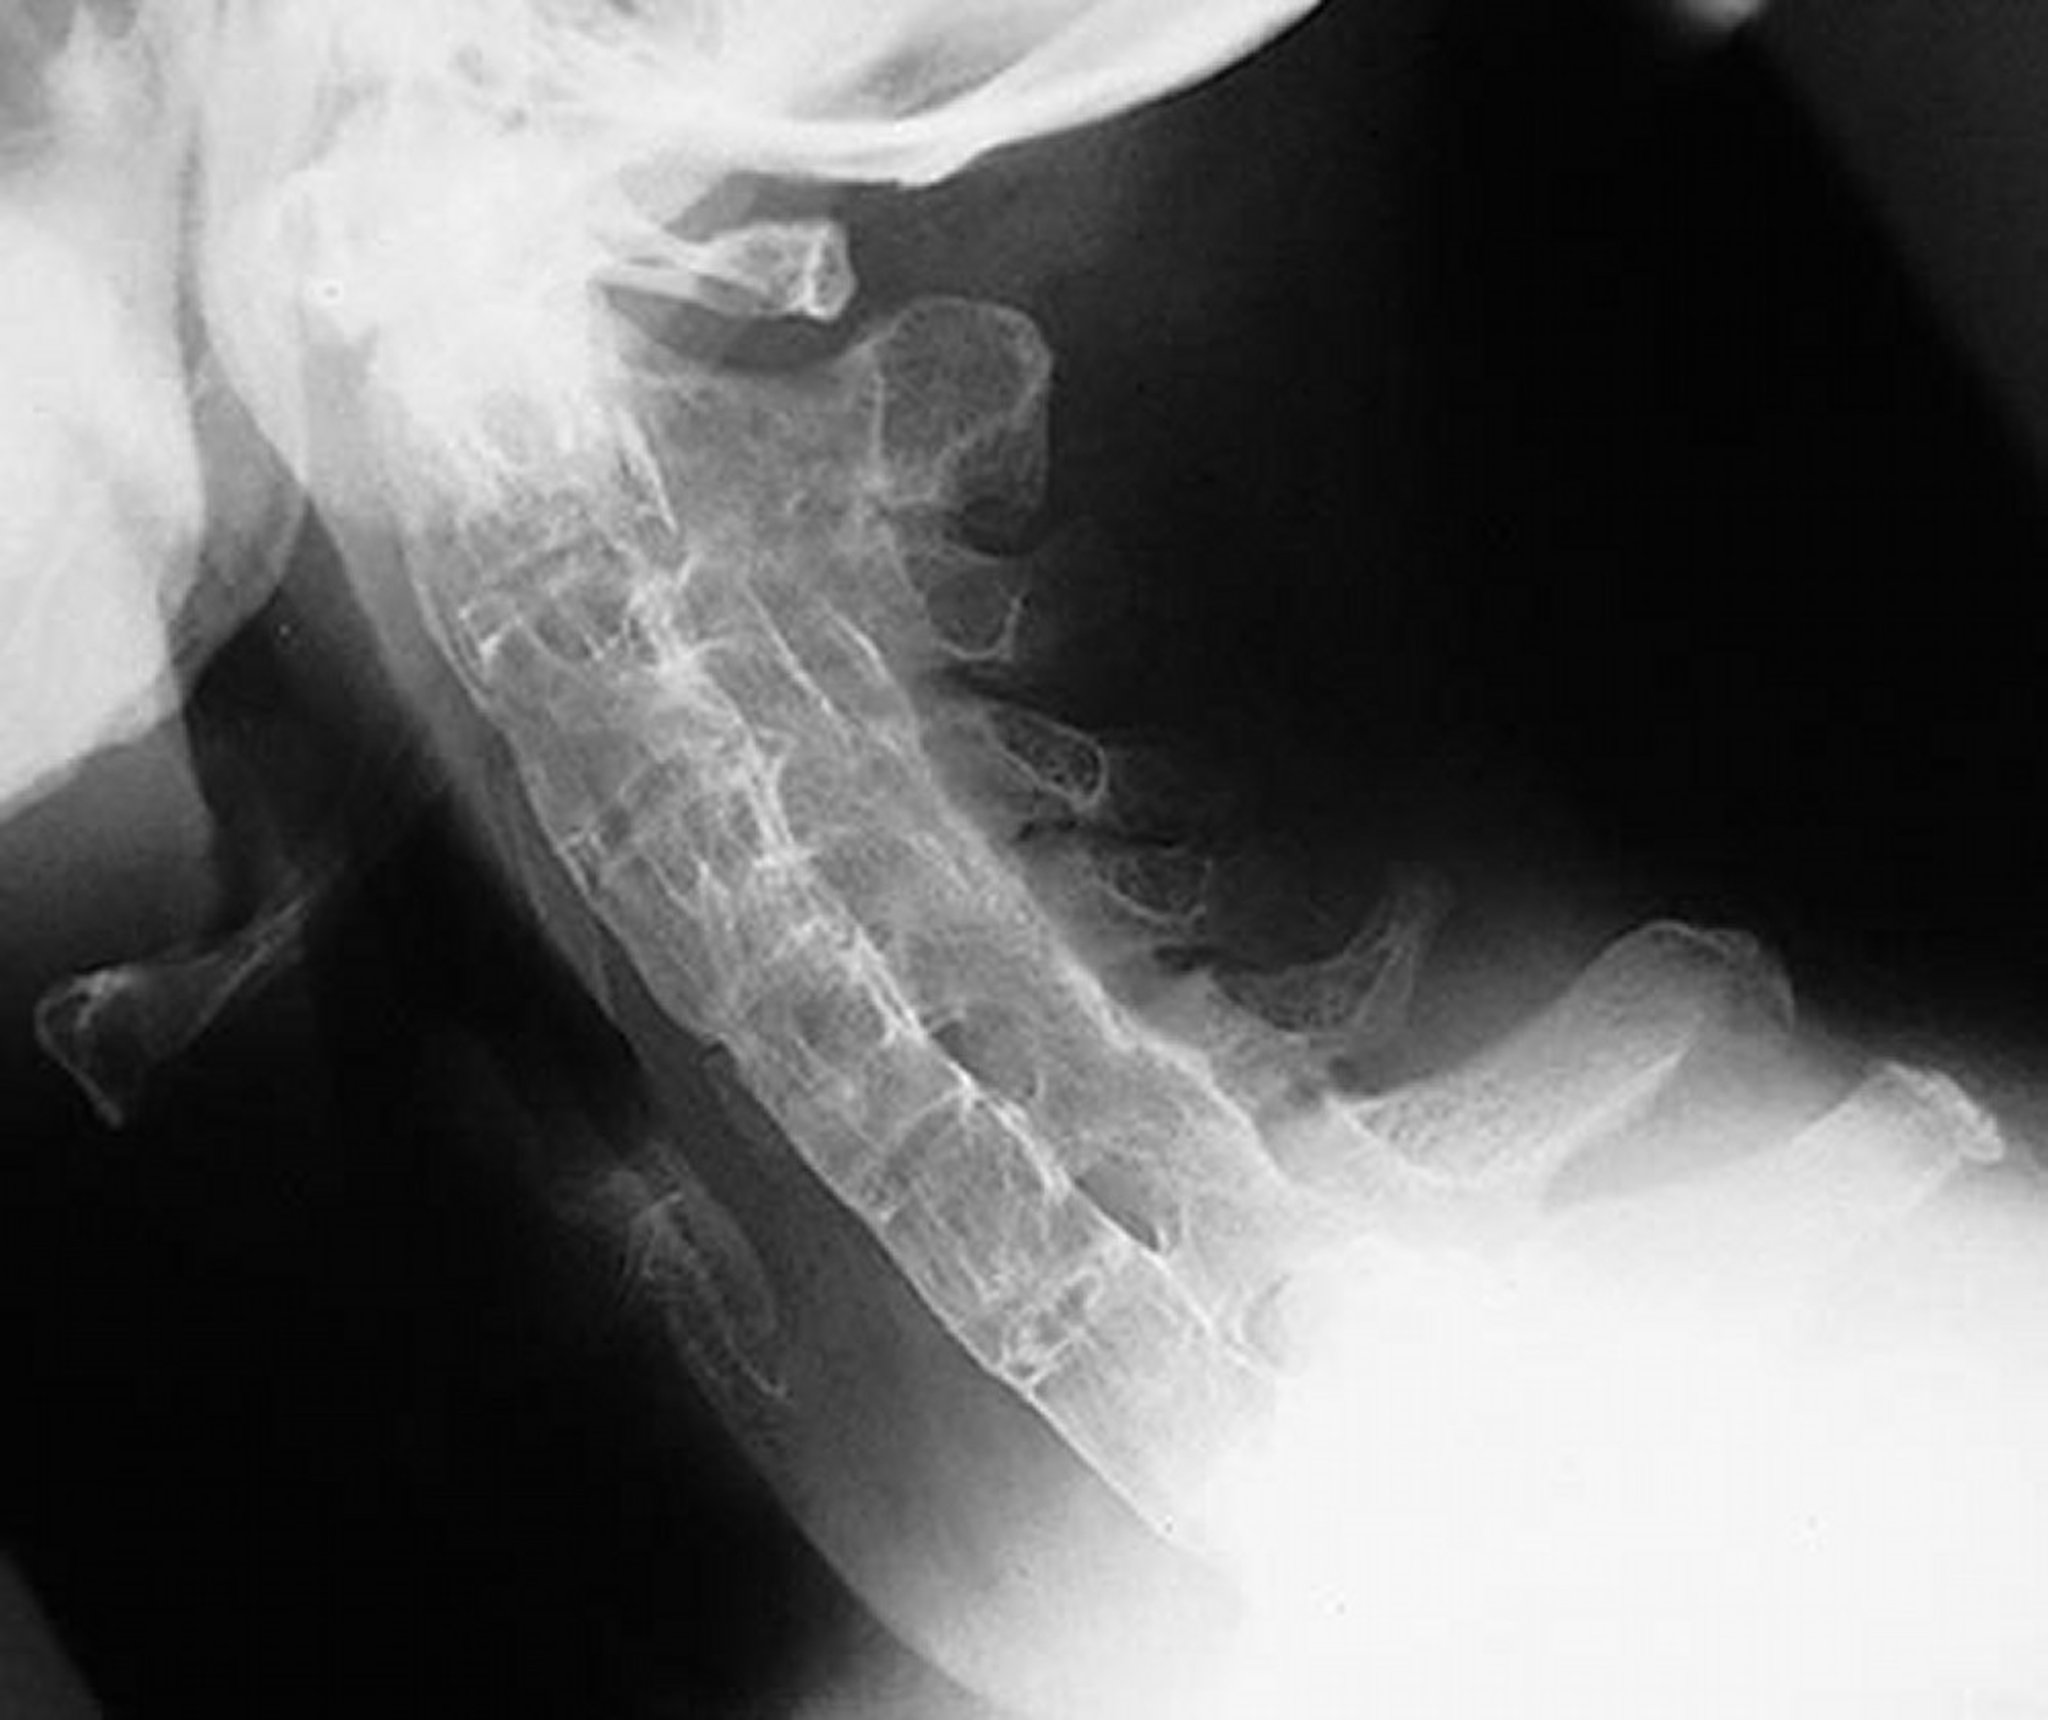

Bamboo Spine in Ankylosing Spondylitis

This lateral view of the cervical spine shows a rigid cervical spine in a patient with severe, long-standing ankylosing spondylitis. The spine is completely ankylosed (“bamboo spine”) due to syndesmophytes, fused facet (apophyseal) joints, and paraspinal ligamentous calcification.